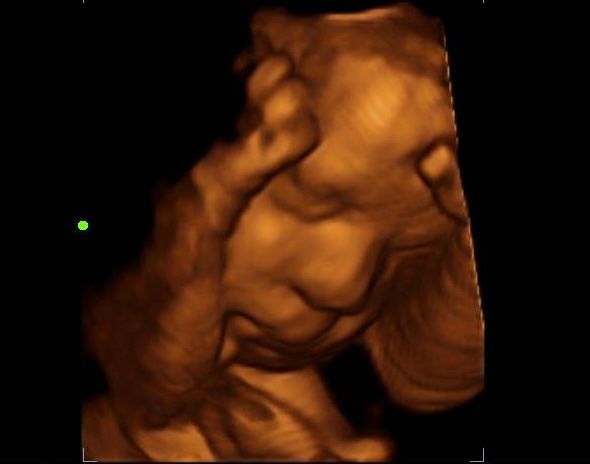

2d, 3d,4d & HD live

At your appointment, we connect directly to your home TV via HDMI, so everyone can enjoy a crystal-clear view. You’ll receive printed keepsake photos in the mail, plus digital images and video recordings delivered straight to your email.

Enjoy a private, affordable ultrasound from the comfort of your home, perfect for moms between 7–41 weeks. Share the moment with loved ones by connecting directly to your TV for real-time viewing in 2D, 3D, or 4D. Ideal for baby showers or gender reveal parties!